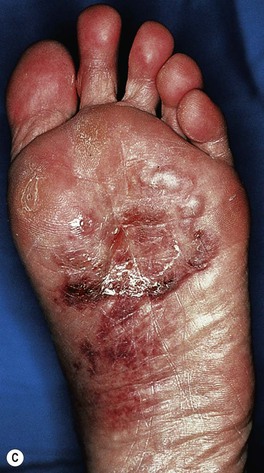

• Tinea pedis (Fig. 64.8).

– Three major types: (1) interdigital – erythema, scaling, and maceration in the web spaces, especially the two lateral web spaces, which have the most occlusion; can be accompanied by fissures as well as superimposed bacterial infection; (2) moccasin – diffuse scaling and erythema that extends onto the lateral aspect of the feet; and (3) inflammatory (vesicular) – vesicles and bullae, especially on the medial aspect of the plantar surface.

– Occasionally, especially in immunocompromised and diabetic patients, a more severe ulcerative toe-web infection can occur where there is both a dermatophyte and a bacterial (e.g. pseudomonal) infection; see discussion of gram-negative toe-web infection in Chapter 61.

Fig. 64.8 Tinea pedis. Diffuse scaling in the moccasin type (A), maceration between the third and fourth toes in the interdigital form (B), and erythema, scale-crust, and bullae in the inflammatory form (C). The patient in (A) also has involvement of the right hand (i.e. one hand–two feet tinea). B, Courtesy, Jean L. Bolognia, MD.